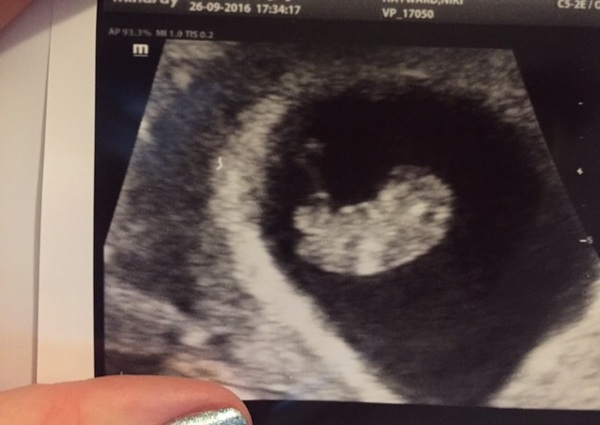

I had my private scan last night and saw a wriggly little blob Smile they dated my at. 9 weeks due 1st may. Can I still stay in this group please ladies. Also would love a Facebook group.

summerskittles91 · 27/09/2016 13:12

Ahh what a lovely photo Niks2026 Looks like a bigger version of my scan at 7 weeks, I named the baby jelly bean as thats what it looked like at the time haha and yes of course you can stay in the group! i reckon due dates will be moving back and forth for a a lot of people.

Great scan photo niks!